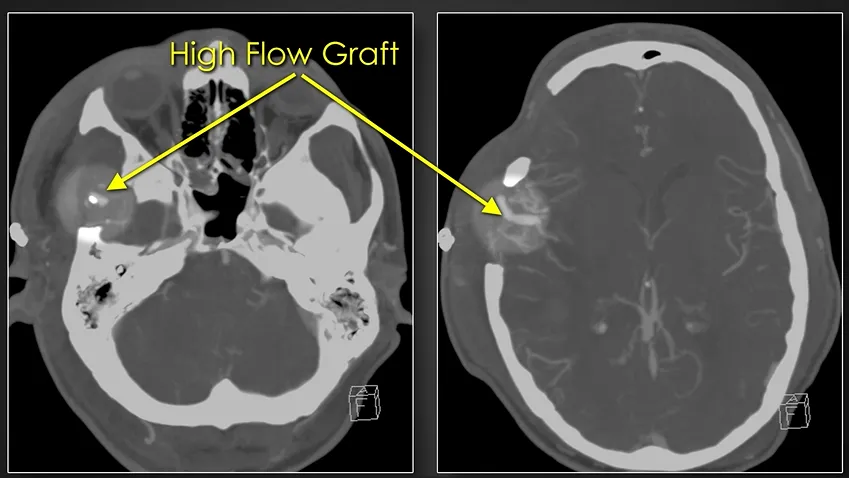

手术实施右额颞开颅,术中注意保护颞浅动脉。完成硬膜外暴露后,于卵圆孔外侧的中颅窝底钻一骨孔。随后解剖外侧裂,分离出其中较粗大的M3分支。通过内镜技术获取大隐静脉移植物,将其一端与颈外动脉进行吻合,另一端则经中颅窝底骨孔形成的隧道穿行,与较粗大的M3分支行端侧吻合。动脉瘤被成功夹闭,受累的较细小M3分支被离断,并与颞浅动脉行端端吻合。术中吲哚菁绿荧光血管造影证实两处搭桥血管均保持通畅。术后患者接受了规范的抗生素治疗及二尖瓣置换术。

术后影像